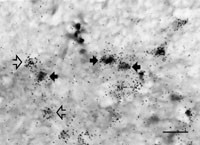

Våra studier har också visat att östrogenreceptorerna framför allt finns i de neuron som producerar den kroppsegna opiaten enkefalin (11) (fig 2). De enkefalinproducerande neuronen fungerar som lokala interneuron och förmedlar både pre- och postsynaptisk hämning av de celler som leder smärtsignaler. Neuronen påverkas av stimulering av såväl perifera nervtrådar som av nedåtgående nervtrådar från smärthämmande centra i hjärnstammen och är en avgörande komponent i det kroppsegna smärthämmande systemet. Genom påverkan på bildningen och frisättningen av enkefalin i dessa neuron regleras alltså smärtkänsligheten. Genen för enkefalin innehåller en sekvens som östrogenreceptorn specifikt kan binda till och därmed reglera uttrycket av enkefalin-mRNA. Vi har i en vehikelkontrollerad studie visat att en perifer injektion av östradiol ger en kraftig ökning av mängden enkefalin-mRNA i ryggmärgen hos honråttor redan efter några timmar (12). Tillsammans med tidigare resultat pekar detta fynd på en tänkbar mekanism för östrogenets smärtmodulerande effekt (fig 3).